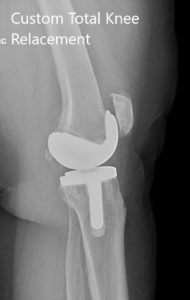

Postoperative X-ray showing the AP view of both knees

Postoperative X-ray showing the lateral views of both knees.